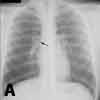

Inspiratory (A), expiratory (B), and lateral (C) chest radiographs confirmed the diagnosis of an endobronchial foreign body. Bronchoscopy revealed a blue pushpin obstructing the right bronchus intermedius and facing proximally into the large airways (D). The larynx, trachea, carina, and left main bronchus were not affected.

Chest radiographs may demonstrate air trapping, atelectasis, or consolidation and are suggestive of a radiopaque foreign body.4 In older children like this patient, chest radiographs should be obtained during inspiration and expiration. Fluoroscopy may be needed in young children. In a 10-year retrospective study, plain chest radiographs revealed a foreign body in only 23.56% of patients.5 In another retrospective study, chest radiographs were normal in 56% of children with tracheal foreign bodies.6